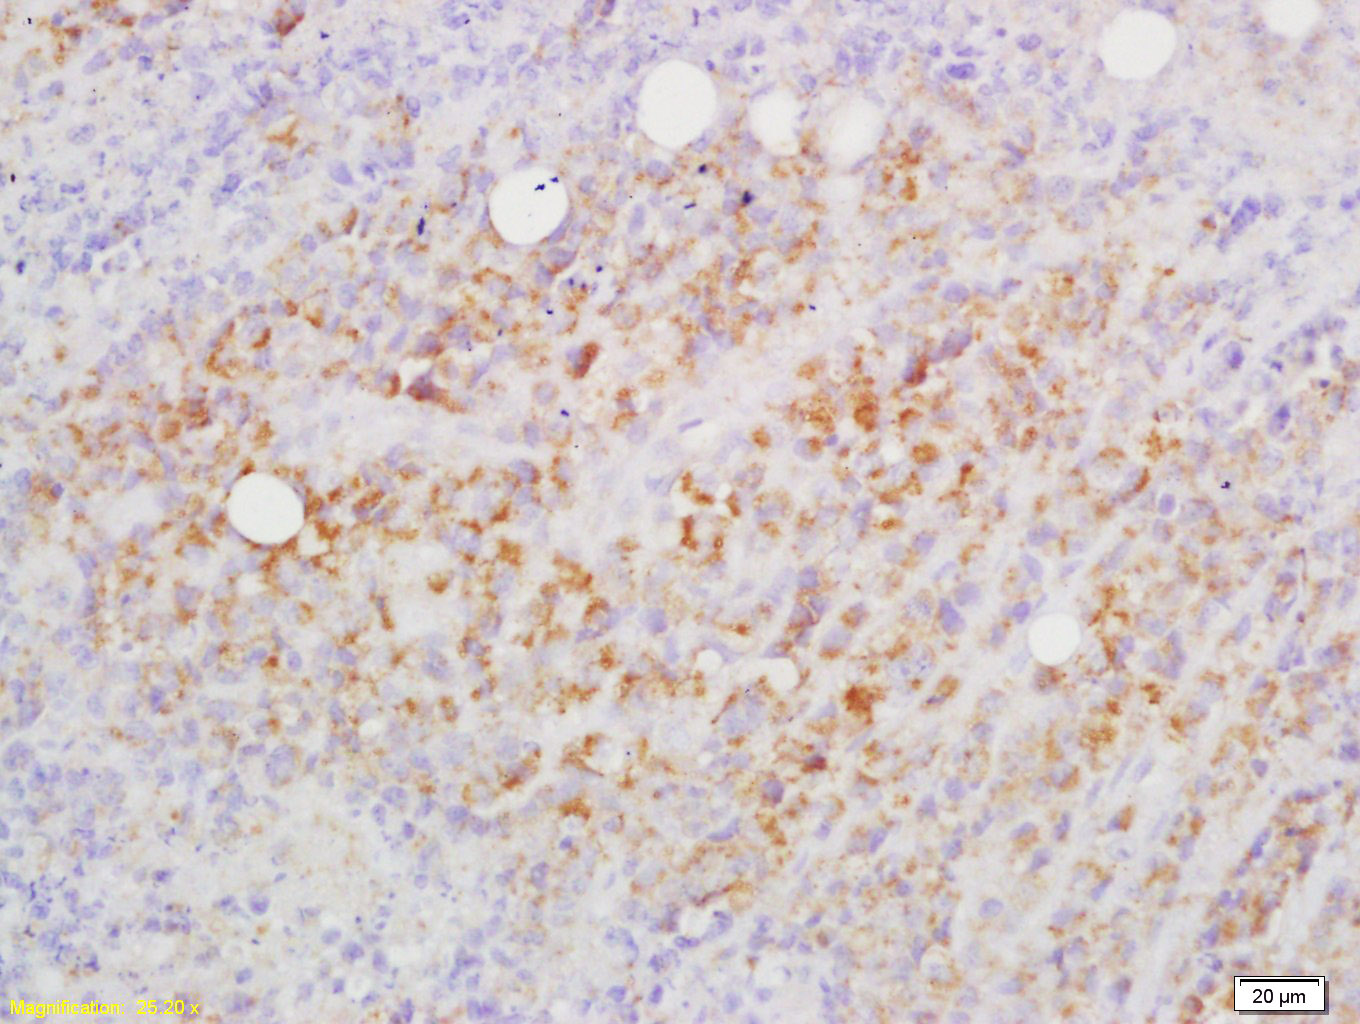

Tissue/cell: mouse lymphoma; 4% Paraformaldehyde-fixed and paraffin-embedded; Antigen retrieval: citrate buffer ( 0.01M, pH 6.0 ), Boiling bathing for 15min; Block endogenous peroxidase by 3% Hydrogen peroxide for 30min; Blocking buffer (normal goat serum,C-0005) at 37℃ for 20 min; Incubation: Anti-CD82 Polyclonal Antibody, Unconjugated(bs-1470R) 1:200, overnight at 4°C, followed by conjugation to the secondary antibody(SP-0023) and DAB(C-0010) staining